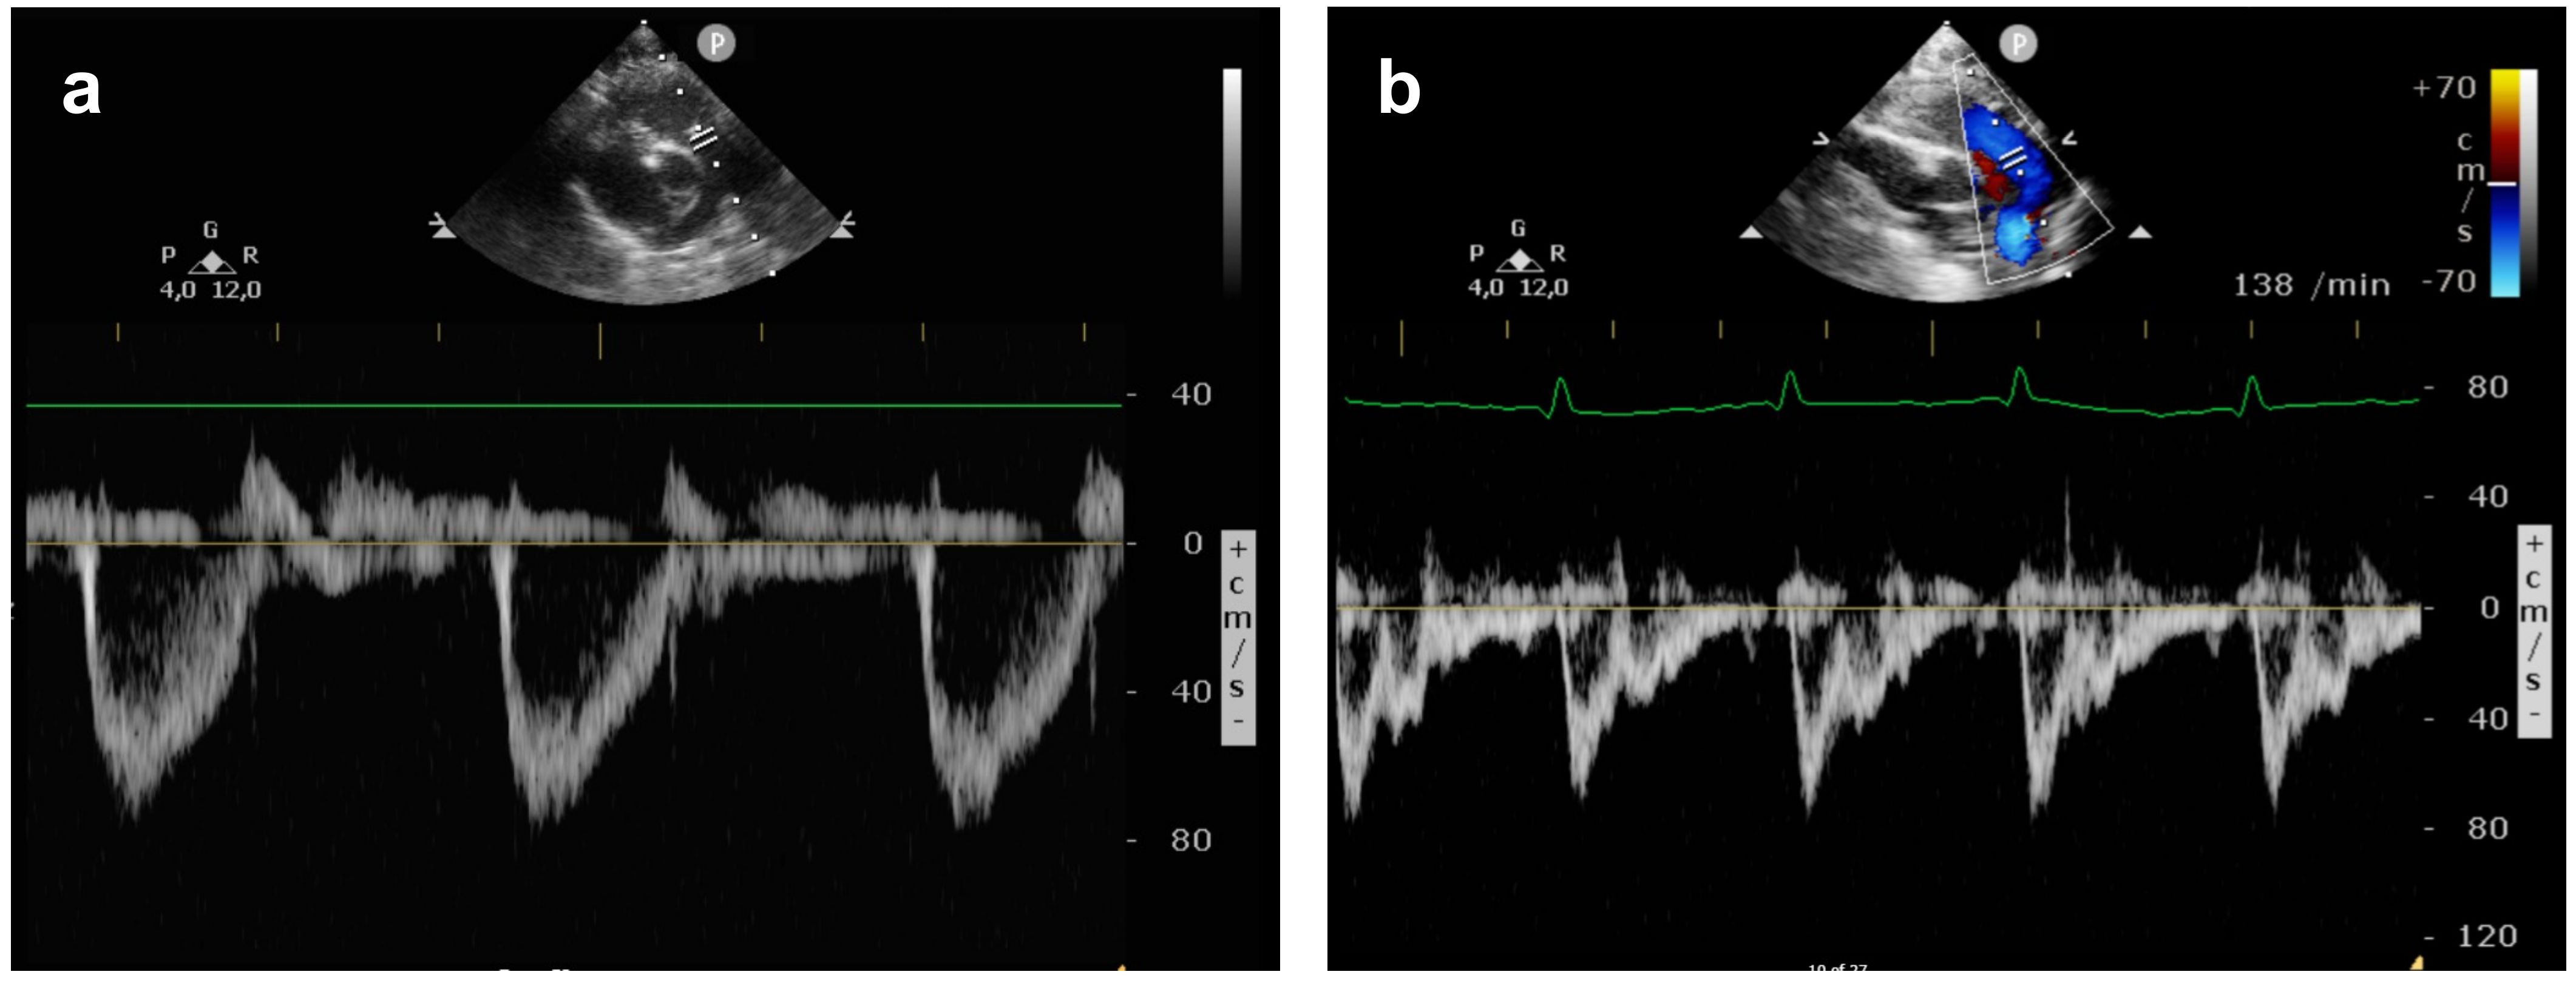

The pulmonary arterial pressure (PAP) was graded as <⅔ systemic pressure (mild PH), ⅔ to systemic pressure (moderate PH), or suprasystemic pressure (severe PH) as described by Keller et al. [3]. Assessment of PH included: (1) DA flow pattern; (2) intraventricular septum position; and (3) calculation of right ventricular systolic pressure from the TR jet with an estimation of 5mmHg for right atrial pressure. The angle of insonation was kept below 20°. To obtain PAAT:ET measurements, the main pulmonary artery (PA) was identified in the parasternal short axis view or from the subcostal window and the echo transducer was placed directly distal to the pulmonary valve. PAAT was measured by PW Doppler from the beginning of systolic flow in the main PA to the point of the highest velocity during systole, while the ET was measured as the duration of the systolic blood flow (Figure 1). Using the incorporated measurement calipers, both values were expressed in milliseconds (ms).

Figure 1.

Pulmonary artery flow pattern on the first day of life: (a) normal pulmonary artery flow in a healthy neonate showing a PAAT:ET of 0.335; (b) pulmonary artery flow in a CDH neonate with severe pulmonary hypertension and a PAAT:ET of 0.146.